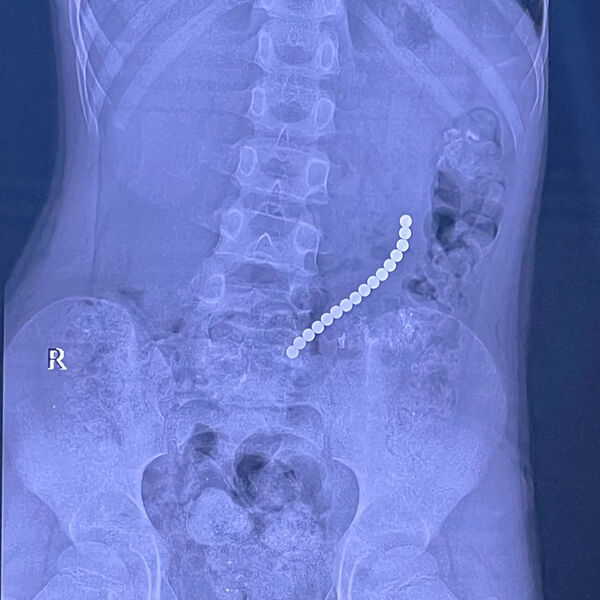

Российский школьник проглотил 16 магнитных шариков

В Иркутске спасли восьмилетнего мальчика с 16 магнитами в желудке и кишечнике

Врачи Иркутской областной детской клинической больницы спасли восьмилетнего пациента, который проглотил магниты. Об этом сообщил главврач больницы, член-корреспондент РАН Юрий Козлов на своей странице во «ВКонтакте».

Медик отметил, что ребенок поступил в медучреждение с жалобами на «острый живот». На обследовании специалисты обнаружили 16 магнитов, которые соединились между собой в различных сегментах внутренних органов.

«Очень редкое сочетание: одни магниты находились в желудке, другие — в начальном отделе тонкой кишки. Это привело к образованию фистулы — сообщению между желудком и кишкой», — поделился Козлов.

С помощью технологий минимально-инвазивной хирургии врачи извлекли инородные предметы, разделили органы и восстановили их целостность.